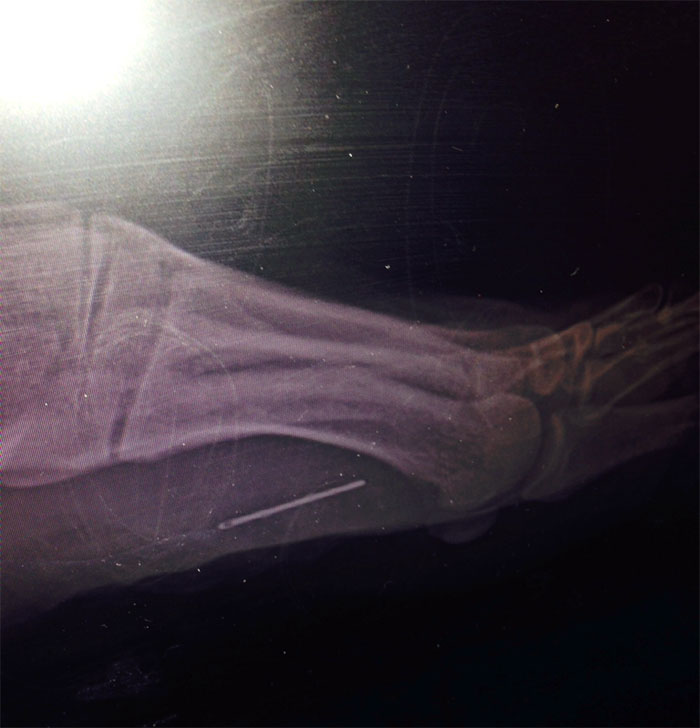

A Woman I Work With Had An X-Ray Done To Her Foot For Her Arthritis... Found This Surprise. Apparently It's Been There For Over 30 Years